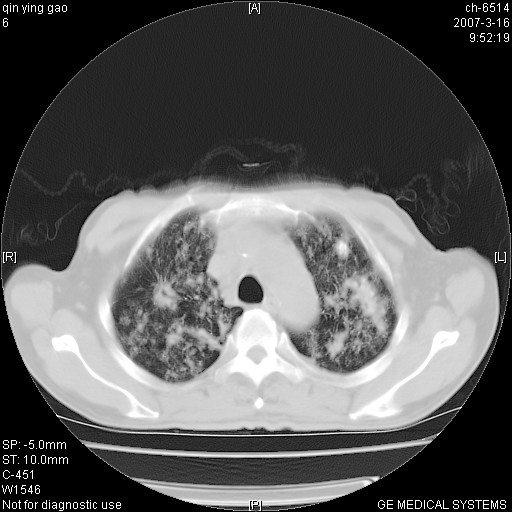

男,64岁.乏力2个月,畏寒、发热1月余。体重下降。血沉加快,白细胞不高。

两中上肺见有广泛新老不一的结节灶,并伴有纤维索条影,血沉加快,白细胞不高,首先考虑结核。

双肺以中上肺野为著斑片状.结节壮密度增高影 左上肺前段可见小类圆钙化灶 纵隔淋巴结无明显肿大

双肺可见大小不等结节状密度增高影,密度不均,分布不均(双肺上叶为著),亚急性血行播散性肺结核.

(本例特征:以大小不等结节为主,主要分布在双上肺,并部分病灶融合成较大结节,期间搀杂诸多细小结节。从病灶特点与分布形式分析,更趋向于感染。)

男,64岁.乏力2个月,畏寒、发热1月余。体重下降。血沉加快,白细胞不高。 双肺可见大小不等结节状密度增高影,密度不均,分布不均(双肺上叶为著),亚急性血行播散性肺结核.

中上肺野密布棉团状影,以胸膜下区为界,边缘模糊,可能是小叶或腺泡渗出及实变。全肺野弥漫分布网线样影及细小粟粒样影,可能是细支气管炎及间质内炎症。综合分析应首先考虑气道播散性感染,而肺内多处斑点性钙化,强烈提示陈旧结核复发并支气管播散。建议详细讯问病史